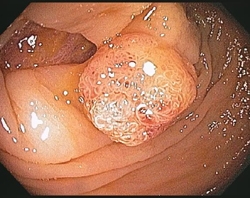

Ο πολύποδας είναι μία μάζα κυττάρων,ένα μικρό εξόγκωμα, της εσωτερικής επένδυσης του παχέος εντέρου .Ένας πολύποδας σε σχέση με την εσωτερική επιφάνεια του εντέρου μπορεί να είναι επίπεδος ή ανυψωμένος. Υπάρχουν διάφοροι τύποι πολυπόδων, και μερικοί μπορούν τελικά να αναπτυχθούν με την πάροδο του χρόνου και να γίνουν καρκίνος.

Κολονοσκόπηση: Μια διαδικασία κατά την οποία ένας μακρύς, λεπτός, εύκαμπτος σωλήνας τοποθετείται από τον πρωκτό μέσα στο παχύ έντερο. Ο σωλήνας διαθέτει μια κάμερα που δείχνει εικόνες σε μια οθόνη και ένα εργαλείο για να κόψει τυχόν πολύποδες.

Όταν εντοπιστεί ένας πολύποδας, ο γιατρός θα το αφαιρέσει και θα το εξετάσει για να δει τι είδους είναι. Οι περισσότεροι πολύποδες αφαιρούνται κατά τη διάρκεια μιας κολονοσκόπησης. Ο γιατρός σας θα καθορίσει πότε θα πρέπει να πραγματοποιήσετε μια επανάληψη της εξέτασης ελέγχου βάσει του αριθμού των πολύποδων, του τύπου των πολύποδων και των παραγόντων κινδύνου.